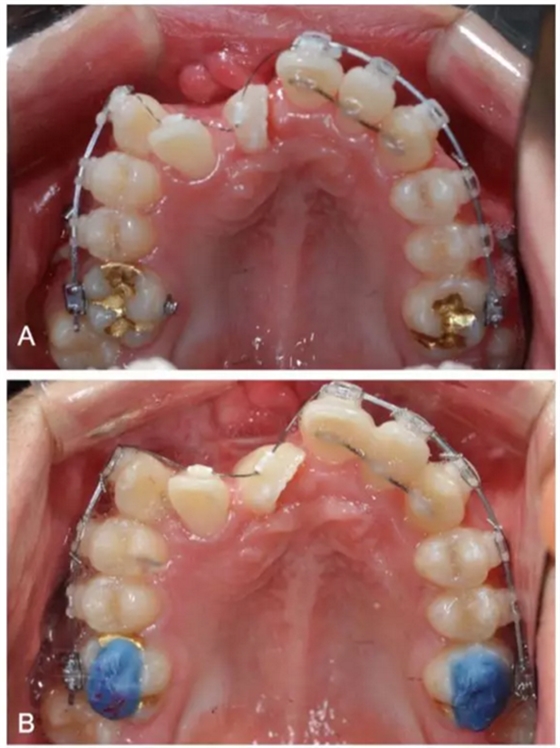

一期手術主要是牽引側切牙和尖牙:于上頜前牙區(qū)唇側作切口,翻全厚瓣;腭側面較小;在尖牙唇側、側切牙腭側粘扣掛結扎絲牽引,通過一輔助鈦板及樹脂等連接至弓絲上;采用閉合式導萌技術,將皮瓣復位縫合,僅結扎絲穿過粘膜;2周內軟組織得以愈合,牽引開始。先通過正畸力,近中移動側切牙,遠中移動尖牙。10個月后,阻生牙牙冠萌出,側切牙、尖牙的易位得以矯正。

二期手術主要是牽引中切牙:于上頜前牙區(qū)腭側作切口,翻全厚瓣,在切牙唇側粘扣掛結扎絲牽引;軟組織愈合后,牽引開始。為施加合適的垂直向力,在下頜前牙區(qū)放置C型管,掛橡皮筋牽引。14個月后,切牙牙冠萌出。使用mini管代替托槽,對切牙、尖牙進行矯治;矯治過程采用輕力,0.014-in鎳鈦絲。

第三階段:

中切牙旋轉矯正后,患者至牙周科醫(yī)生處行右上前牙區(qū)骨增量手術。前牙區(qū)翻瓣后,使用Bio-oss及膠原膜覆蓋所有骨壁開窗或較薄處,皮瓣復位縫合。2周后,繼續(xù)進行正畸矯治。